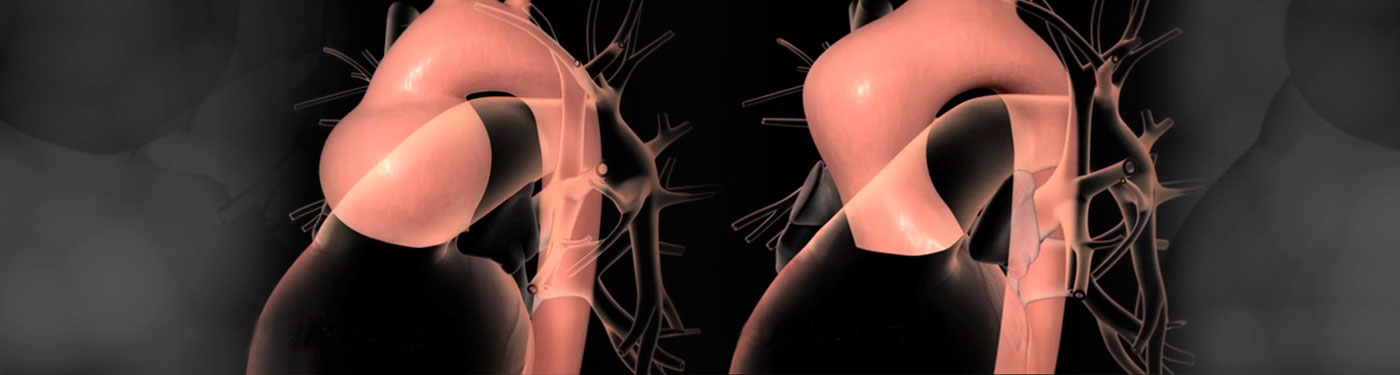

- Ανευρύσματα θωρακικής αορτής μπορεί να παρουσιαστούν σε διάφορα μέρη της θωρακικής αορτής. Το ανεύρυσμα της ρίζας της αορτής μπορεί να προκαλέσει ανεπάρκεια αορτικής βαλβίδας. Άλλη πάθηση της αορτής, ή οποία μπορεί να εξελιχθεί σε ανεύρυσμα, είναι ο διαχωρισμός (σκίσιμο) της αορτής πού αποτελεί μία οξεία βαριά, καταστροφική πάθηση του καρδιαγγειακού συστήματος. Οι δυο σημαντικότεροι παράγοντες του αορτικού διαχωρισμού είναι ή υπέρταση και ή εκφύλιση του μέσου χιτώνα του τοιχώματος της αορτής από κάποιο συγγενές νόσημα. Άλλοι παράγοντες μπορεί να είναι ή εγκυμοσύνη (ιδιαίτερα κατά το τρίτο τρίμηνο της κύησης) και ο τοκετός.

Ανεύρυσμα Ανιούσης Αορτής σε διάφορες απεικονίσεις

Διαχωρισμός Αορτής

Ψευδοανεύρυσμα Ανιούσης Αορτής